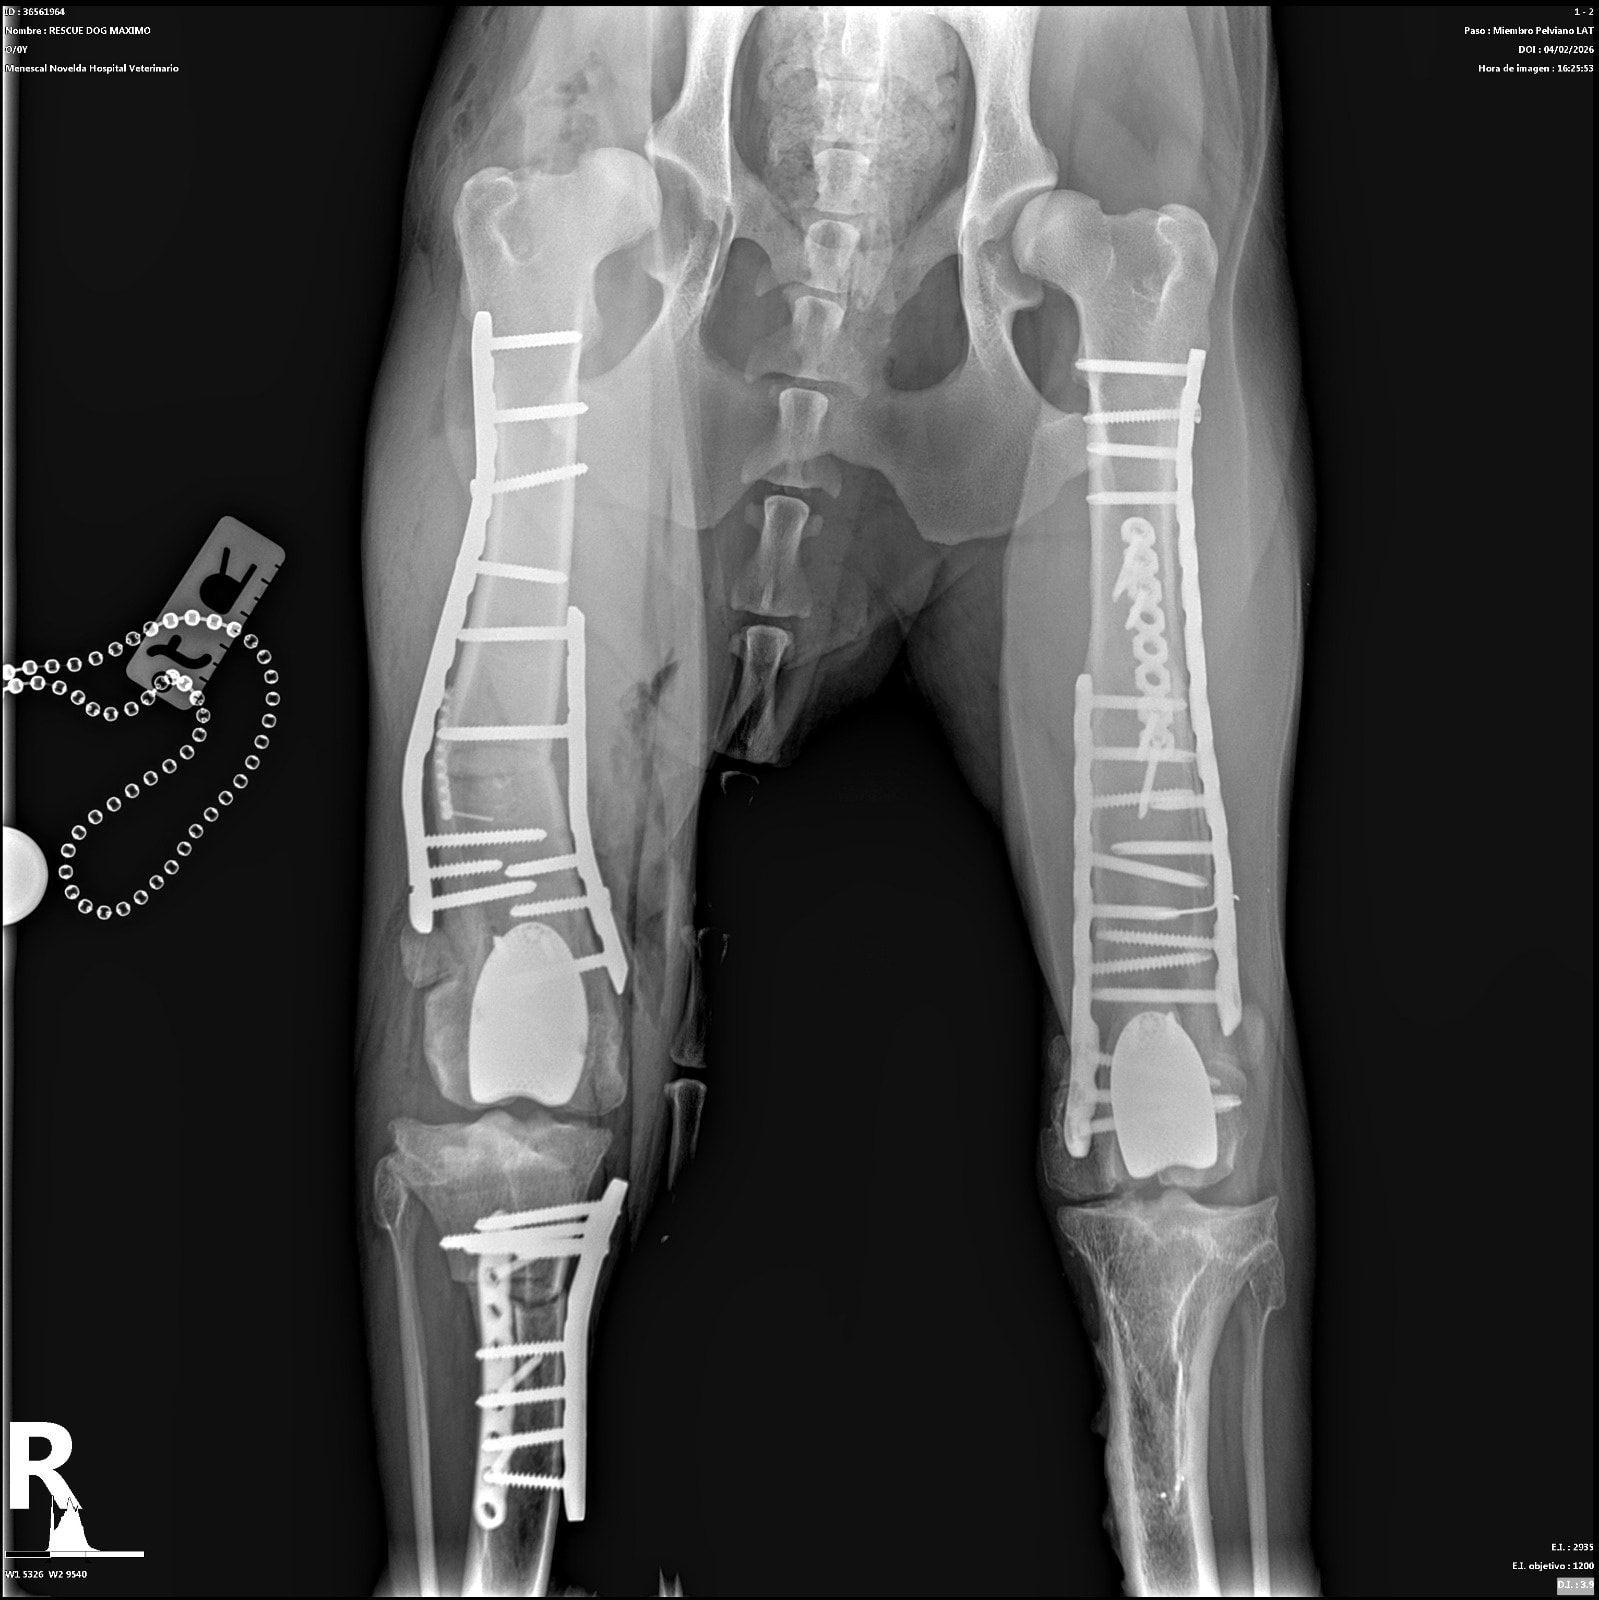

Abbiamo allegato fattura e lastre post-operatorie in totale trasparenza

CANGU è uno dei nostri grandi combattenti. Lo abbiamo salvato in Spagna molto tempo fa, quando viveva in condizioni disperate: grave dolore e difficoltà nei movimenti, zero prospettive senza un intervento immediato. Da allora abbiamo fatto tutto ciò che era possibile per offrirgli una vita degna. Abbiamo già finanziato due interventi complessi al primo arto posteriore:

– il primo intervento purtroppo non ha portato alcun miglioramento;

– il secondo, una protesi totale del ginocchio, ha finalmente dato risultati positivi e oggi quell’arto gli permette una migliore stabilità.

Ora ci troviamo di fronte ad passo indispensabile per garantirgli una qualità di vita accettabile: intervenire sul secondo arto posteriore, ancora in condizioni critiche. Lasciarlo così significherebbe condannarlo a un dolore costante, a un peggioramento progressivo con un carico eccessivo sulla prima protesi e a una vita senza autonomia. Operarlo, invece, significa dargli una possibilità reale di camminare meglio, di muoversi, di vivere dignitosamente. L’intervento previsto è un DFO con la protesi completa del secondo ginocchio. Il costo è di 8.098 euro (allegato preventivo). Non otterremo un cane “perfetto”: Cangu avrà comunque dei limiti, perché per un recupero totale servirebbero protesi anche a livello delle anche. Ma questo intervento rappresenta la parte fondamentale del suo percorso di riabilitazione, quella che può migliorare la sua quotidianità.